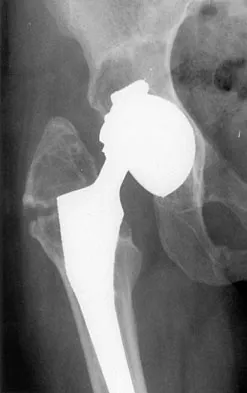

Figure 36 shows the radiograph of a patient who has hip pain and is unable to ambulate. What is the most appropriate management for this patient?

Explanation

The patient has a periprosthetic fracture of the greater trochanter - Vancouver A. The reason for the fracture of the greater trochanter is the extensive periarticular osteolysis that has occurred as a result of polyethylene wear. The latter is demonstrated by eccentric seating of the large femoral head in the acetabulum. The most appropriate management is to reverse the osteolysis process, which involves exchange of the acetabular liner with or without revision of the other components depending on their fixation and position. The greater trochanter can also be fixed during revision surgery. Duncan CP, Masri BA: Fractures of the femur after hip replacement. Instr Course Lect 1995;44:293-304.